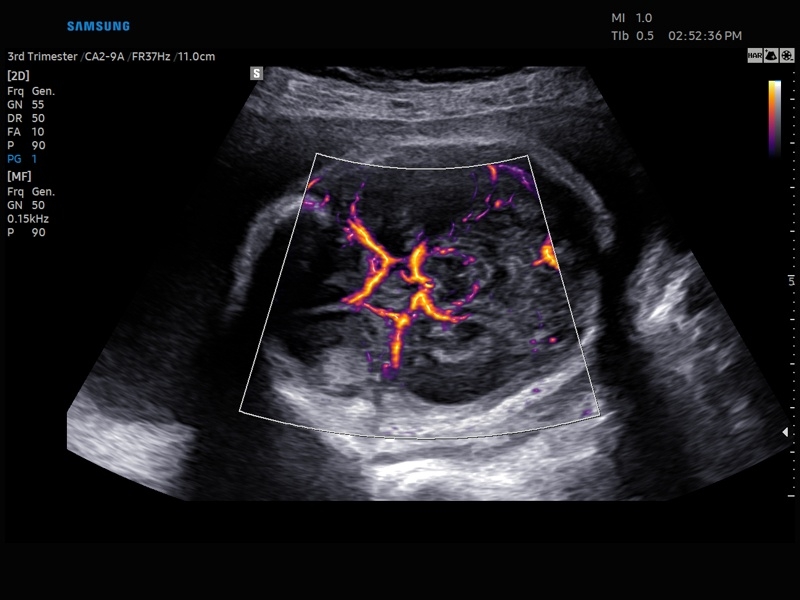

• Модуль LumiFlow – программа отображения кровотока с объемной графикой для лучшего понимания архитектоники сосудистого русла.